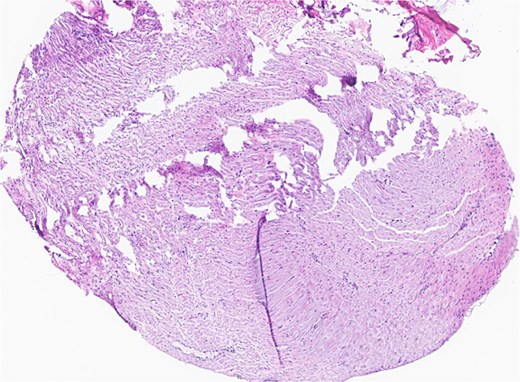

The patient underwent wide local excision of preauricular skin, parotidectomy, and selective left neck dissection (levels I–IV) (Fig. 2). Surgical pathology revealed poorly differentiated SCC involving subcutis, parotid, and surrounding soft tissues. In addition, CLL was found in three intra-parotid lymph nodes (Fig. 3). Immunohistochemistry showed cells positive for CD20, CD5, CD19, CD22, CD23, CD41, and BCL2, and negative for CD3, CD10, CD21, and cyclin D1. Flow cytometry revealed lambda light chain-restricted B-cells, with an absolute clonal B-cell count of 1.01 × 109/l, and 16.7% atypical lymphocytes in peripheral blood.

Left parotid tumor, biopsy: small lymphocytic lymphoma/CLL involving a lymph node.